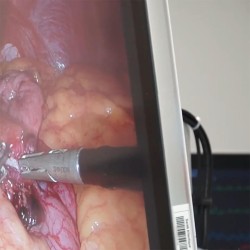

Se faire une sleeve en Tunisie (Endo Sleeve)

La décision de subir une opération Sleeve Tunisie est avant tout motivée par le désir de perdre du poids, tout en répondant également aux problèmes de santé liés à l'obésité et aux pathologies associées.

Opter pour la Tunisie comme lieu idéal pour subir une Sleeve gastrectomie Tunisie est une très bonne décision. Il est à noter que notre taux de satisfaction est tout simplement exceptionnel.